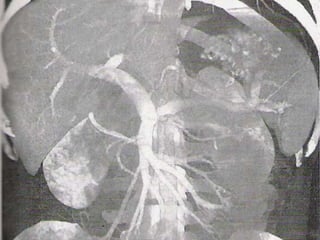

CHRONIC MESENTRIC ISCHEMIA

WITH VASCULAR CALCIFICATION

WITH VASCULAR COLLATERALS

Sagittal subvolume and coronal subvolume MIP images show severe stenosis of

the celiac, superior mesenteric and inferior mesenteric arteries.